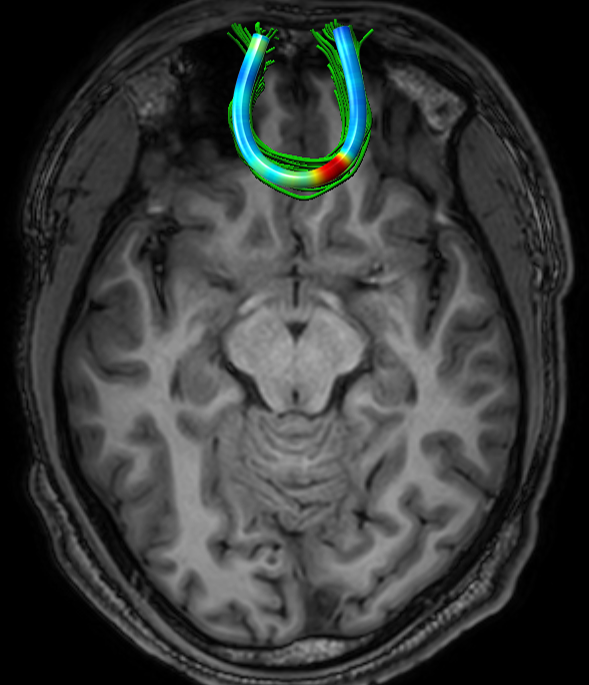

3.2 Football Players Study

We analyzed 13 active professional American-football players (mean age = 28.3, STD = 6.4), with respect to 17 NCs (mean age = 26.1, STD = 2.3). For each subject, four FFDD tract-profiles were computed (based on FA, MD, RD, and AD), for each of the five examined tracts. The standardized FFDD profiles of NCs are shown in Fig. 3. Note that although FFDD values vary along the tracts, their profiles are consistent across subjects.

Fig. 4 presents pointwise group-average and STD of MD-FFDD profiles of football players, demonstrating increased values at the occipital part of the left IFOF, and at the central part of the FMT, compared to NCs. Note that the football group also exhibits higher STD values compared to NCs, at the same areas along the tracts with increased group-average values. This statistical spread indicates that only a subset of the football players group has abnormal FFDD values, as expected.